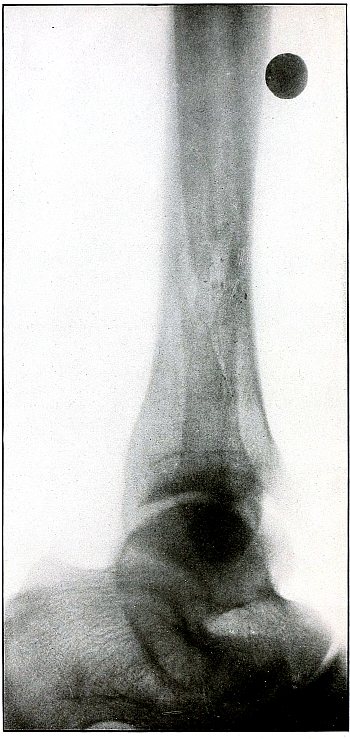

Gunshot fracture, ankle |

154 |